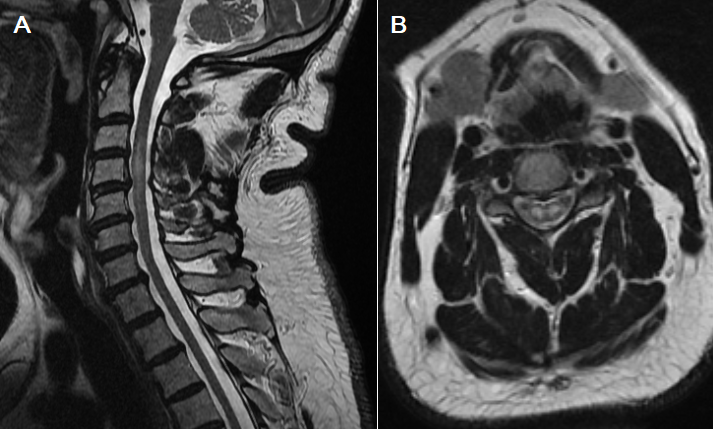

L’infarctus médullaire est un diagnostic relativement méconnu, qui engage à court terme le pronostic, aussi bien vital que fonctionnel du patient. La vascularisation médullaire est l’une des plus complexes de l’organisme en raison du nombre important d’artères qui y contribuent. La rareté des accidents vasculaires médullaires et la faible accessibilité des vaisseaux médullaires aux investigations expliquent que nos connaissances restent limitées. Nous rapportons le cas d’un patient de 62 ans, diabétique de type 2 sous antidiabétiques oraux depuis 13 ans et suivi pour un psoriasis depuis 4 ans, a été amené à l’hôpital dans la nuit par son fils devant l’installation brutal d’un déficit des 2 membres supérieurs. Ce déficit était précédé de cervicalgie aiguë lors d’une montée brutale du patient en pratiquant sa prière quotidienne. A son admission, le patient était conscient, tension artérielle: 120/86mmhg, fréquence cardiaque: 89 battements/min, apyrétique. L’examen clinique révélait une diplégie brachiale flasque. Il n’y avait pas de troubles sensitifs ni de troubles sphinctériens et l’examen des paires crâniens était normal. Une IRM (Imagerie par Résonnance Magnétique) médullaire était réalisée en urgence, mettant en évidence un hyper signal T2 et une diffusion centrale bilatérale réalisant un aspect de « Snake-eyes » (A et B). Le bilan étiologique avait révélé la présence d’une plaque d’athérome à l’origine de l’artère carotide interne gauche. Le diagnostic d’infarctus médullaire sur embolies fibrocartilagineuses a été retenu. Une rééducation fonctionnelle est commencée précocement ainsi qu’un traitement par antiagrégant plaquettaire.